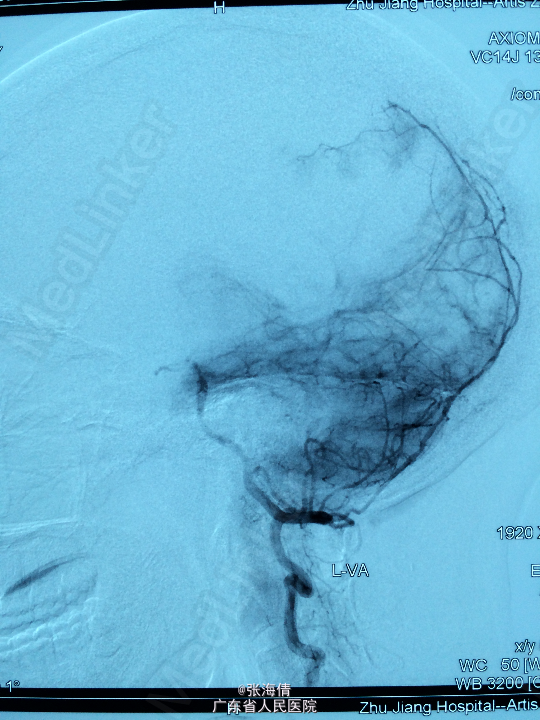

主诉:头晕、恶心6h 病史:患者男,22岁,2年来头晕、恶心症状多次出现,发作频率无明显规律,每次约2 min,无其他不适。6小时前上述症状加重,伴呕吐,呕吐物为胃内容物,外院CT平扫:示右侧颞顶叶见结节状稍高密度影,外院MR提示:平扫示右颞顶叶可见结节状稍长T1混杂T2信号影,大小约2.5 cm×2.1 cm×2.6 cm,边界较清晰,周围见长T1长T2水肿信号,SWI序列病变内未见明显低信号,DWI示信号稍高,增强扫描明显均匀强化,可见分叶,右侧脑室后角轻度受压

查体:全身未触及明显肿大淋巴结。脑膜刺激征:颈项强直,Kernig’S征阳性。 辅助检查:外院CT平扫:示右侧颞顶叶见结节状稍高密度影,外院MR提示:平扫示右颞顶叶可见结节状稍长T1混杂T2信号影,大小约2.5 cm×2.1 cm×2.6 cm,边界较清晰,周围见长T1长T2水肿信号,SWI序列病变内未见明显低信号,DWI示信号稍高,增强扫描明显均匀强化,可见分叶,右侧脑室后角轻度受压

诊断:脑膜瘤 处理:先予DSA以明确肿瘤供血情况,术中脑膜瘤供血丰富,用PVA颗粒超选到供血动脉将其闭塞。后再择期在气管全麻下行脑膜瘤切除术。

术后病理提示:脑膜瘤,WHO I级,瘤组织浸润脑组织。免疫组化:Ki一67(<1%)(+),CK(一),GFAP(一),Vimentin(+),EMA(+),P53(一),ER(一),PR(一)。 讨论:脑膜瘤首选方法为手术切除,手术切除脑膜瘤是最有效的治疗手段,但是由于其供血经常较为丰富,故可先行介入栓塞供血动脉后再行切除,这样可以降低手术风险和手术难度,改善患者手术预后。